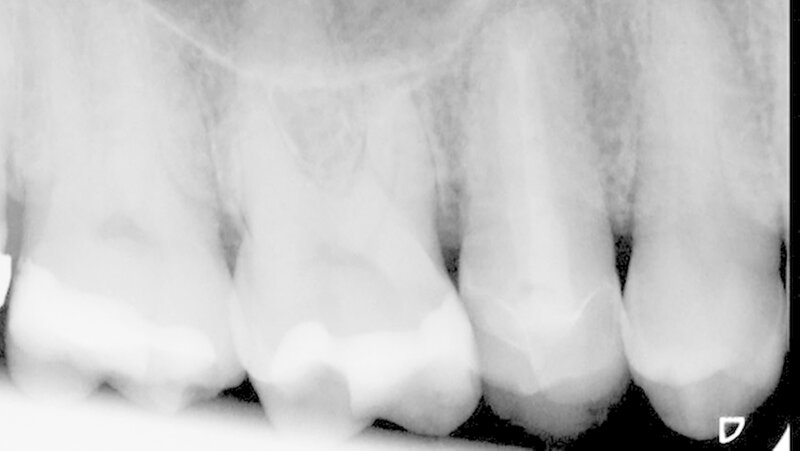

Das röntgenologische Kontrollbild zeigte nach sechs Monaten im Vergleich zur Ausgangssituation im Bereich der entfernten Wurzelspitze und der ehemaligen apikalen Aufhellung eine zunehmende knöcherne Regeneration (Abbildung 10). Zu diesem Zeitpunkt wurde entschieden, den Zahn mit einer Teilkrone zu versorgen, um Scherkräfte zwischen den beiden Höckerspitzen des Zahns zu vermeiden und das Risiko einer erneuten Fraktur zu minimieren. Die Ein-Jahres-Kontrolle zeigte einen konstant klinisch unauffälligen Zahn (Abbildung 11) und eine voranschreitende knöcherne Ausheilung im apikalen Bereich (Abbildung 12).